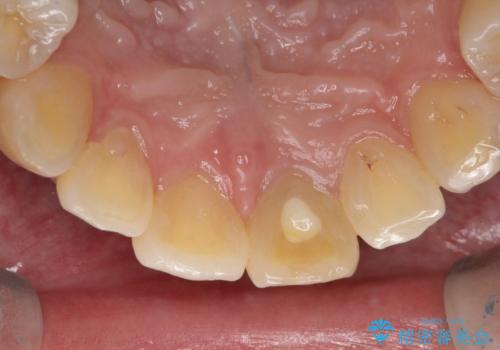

- 前歯が、ポロポロ欠けてくることを主訴で来院された女性です。

以前に根の治療しましたが、最近になって色なども気になり来院されました。

神経の治療をしている歯は、時間と共に色がどんどん変色していきます。

また、神経、血液供給がなくなってしまう影響から歯も脆くなっていってしまうため、歯が割れてしまうリスクもあります。